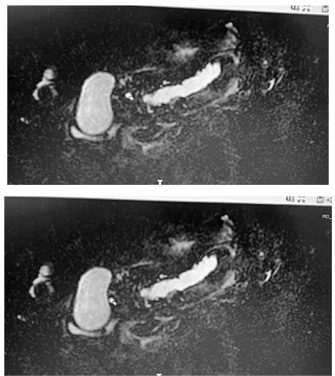

Uma mulher de 62 anos de idade, com dor epigástrica de leve intensidade há seis meses, não teve melhora significativa com o uso de sintomático, porém também não teve agravamento dos sintomas. Nega emagrecimento e não tem outras queixas significativas. Histórico familiar negativo para câncer. Nega tabagismo ou álcool. Fez endoscopia digestiva normal. Exame de sangue específico: leucograma 10 mil/mm3 ; glicemia 110; amilase 320; lipase 200; CEA 1.2; Ca 19.9 16; e bilirrubina total 0,9. Apresentou o exame abaixo, uma ressonância pancreática.